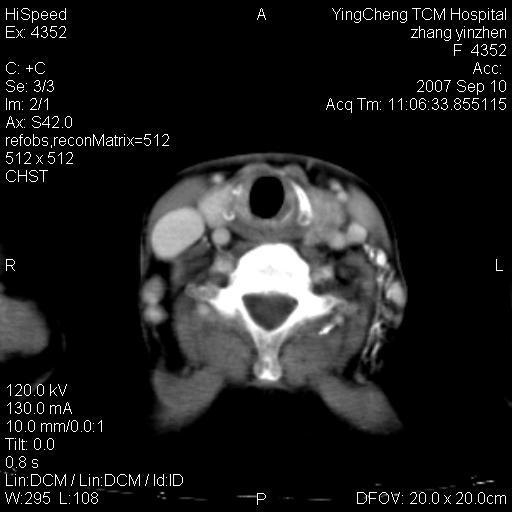

以下是引用卜一在2007-9-18 14:41:00的发言:[br]右肺肿块:毛刺+胸膜凹陷征+供血血管+浅分叶+强化。支持:周围性肺癌 !另:左侧甲状腺腺瘤!

以下是引用夏季在2007-9-18 11:00:00的发言:[br]1。右肺肿块,周围有短毛刺,肺门侧有血管与其相连,胸壁侧有胸膜凹陷征,考虑周围性肺癌 2。左侧甲状腺软组织肿块,内有高密度钙化灶,考虑左侧甲状腺腺瘤。